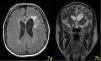

On the 55th day of the treatment, the patient was discharged from the hospital and Ibrutinib 560 mg/day started. An MRI performed on the 210th day of the treatment. The mass disappeared leaving a 20×15 mm malasic area with peripheral gliosis (Figure 7a,b). The patient is now in complete remission and continuing Ibrutinib treatment until further relapses.